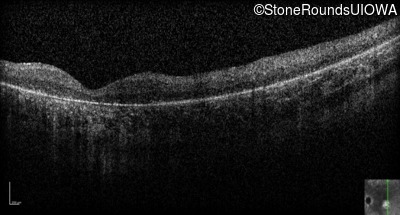

Optical Coherence Tomography - Right - Hand Motion 1' sc

Exemplar / OCT Stack

OCT Stack